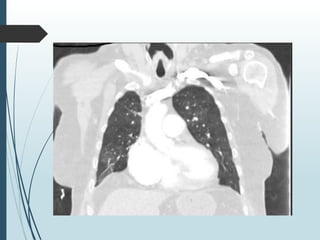

WCM RH Cath 7/2022

 RA 8, PA 52/29 mean 34, Wedge 14

 Cardiac output is 5.2L/min with index of 2.4

 PVR is 3.9 WU, SVR 13 with mean BP of 78

 TPG 20, DPG 15

 pBNP is 148 ( down from 1700)

 Previous cath pre trilogy and diuresis

 RA 22, Mean PAP 68, wedge 28 (group 2)